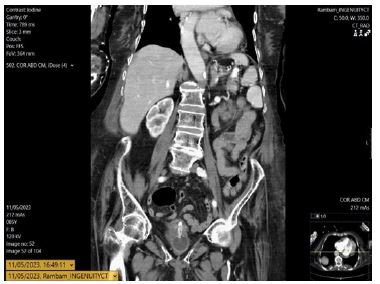

In 2023, 11 years post-insertion, she presented with suspected internal PEG migration. The external stoma was clean, but the tube was absent. Abdominal CT located the tube in the duodenum.

A temporary Foley catheter secured the tract. Subsequent endoscopy did not visualize the tube in the duodenum but found the gastrostomy device within the stomach (Figure 1). A new 14F replacement tube was inserted. The duodenal component seen on CT was presumed likely to pass spontaneously (Figure 2), and the patient was monitored for obstruction.